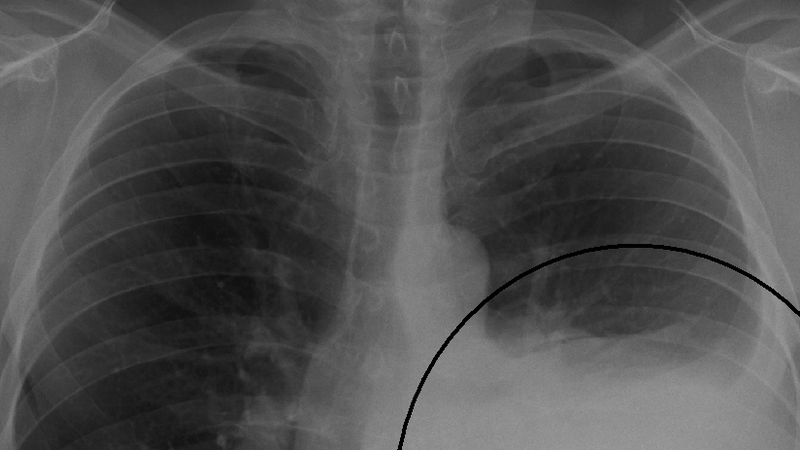

Hơn một nửa số bệnh nhân mắc hội chứng móng tay vàng có bệnh lý đường hô hấp đi cùng. Biểu hiện phổ biến nhất là ho mạn tính, sau đó là tràn dịch màng phổi. Các bệnh lý khác của phổi bao gồm giãn phế quản, viêm phổi tái phát nhiều lần, viêm xoang và xơ phổi.

Tràn dịch màng phổi nhiều và dai dẳng có thể làm giảm đáng kể chức năng phổi cũng như chất lượng cuộc sống của người bệnh. Tràn dịch màng phổi cũng làm tăng nguy cơ nhiễm trùng, suy hô hấp, thậm chí là tử vong. Việc dẫn lưu màng phổi thường xuyên có thể dẫn đến giảm albumin máu, khiến chứng phù nề trở nên trầm trọng hơn và tràn dịch tái phát.